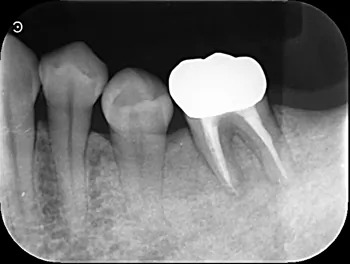

治療後3ヶ月

| 治療経過 | ラバーダム防湿を行い、マイクロスコープを用いて滅菌下で精密な根管治療を行いました。根管内部を完全にきれいにした後、細菌が繁殖しない様に内部を緊密に封鎖(根管充填)をしました。直後はまだ透過像を認めますが、3ヶ月経過後は炎症もほとんど認められず、症状も改善されていました。 患者さんも抜歯をせずに済んだ為、喜んでいました。現在はラバーダム防湿やマイクロスコープ、また場合によってはCT撮影をする事で今までの治療では見落としていた問題を見つける事ができるようになって、治療の成功率を上げることができます。 |